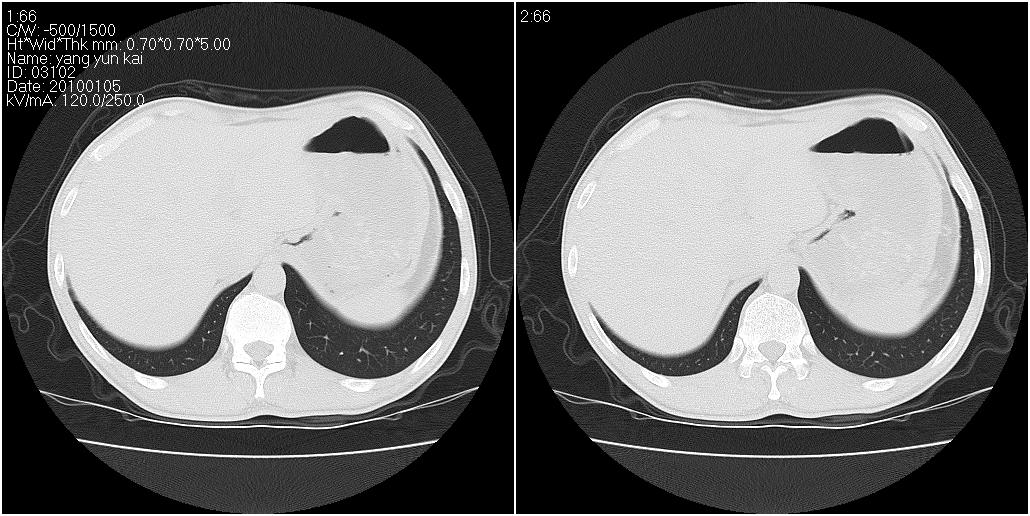

标题: CT23980:男性,47岁。近来咳痰、咳血,血沉增快(40左右),

男性,47岁。近来咳痰、咳血,血沉增快(40左右),痰中未检出结核杆菌。

两肺继发性肺结核并多发性结核球形成,部分病灶内空洞形成。

符合继发性结核表现部分空洞形成并播散